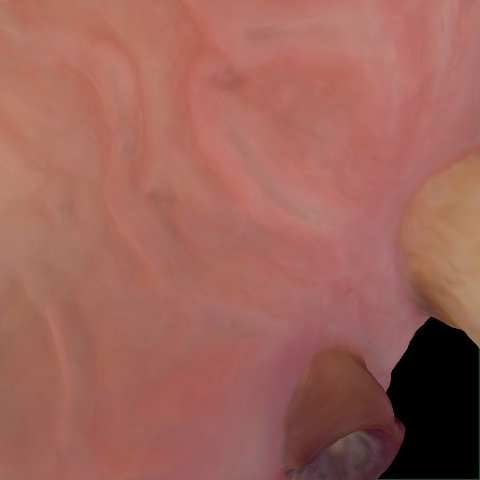

Annotated as "Good"